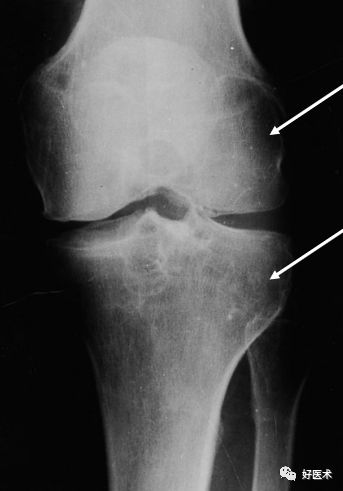

X线

第一期:早期病变,无任何X线表现;

第二期:滑膜炎表现,髌上囊肿胀,因关节积液为血性,故密度稍高;接着出现骨腐蚀和囊性变——实际上是结节在骨软骨上的压迹,以发生在髋关节最为多见;

第三期:进展期,滑膜上有多个软组织结节形成,虽未钙化,但含铁血黄素的密度高,在X线片往往可以显示出结节上轮廓,具有诊断价值。